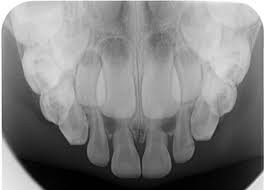

2. How old is the patient with the following X ray?